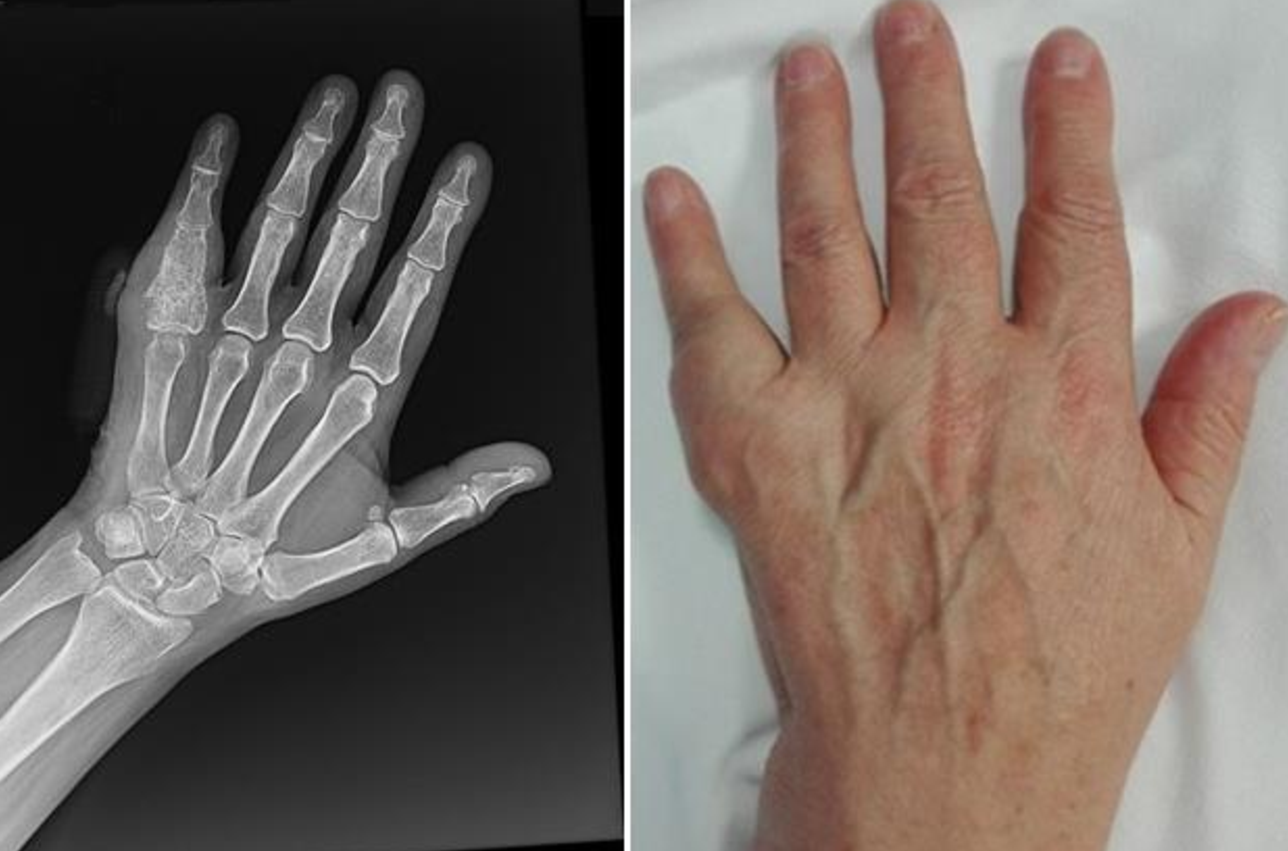

단순 방사선 검사 및 CT, MRI 검사가 진단에 도움이 됩니다. 단순 방사선 검사에서는 주로 뼈가 흡수되어 음영이 감소된 둥근 병변을 보이고 주변피질골이 얇아지면서 부풀어 올라있는 형상을 보이는 경우가 많습니다. 이러한 방사선 검사에서 내연골종으로 추정되면 추가적인 검사를 통해 정확하게 진단하는 것이 필요 합니다.